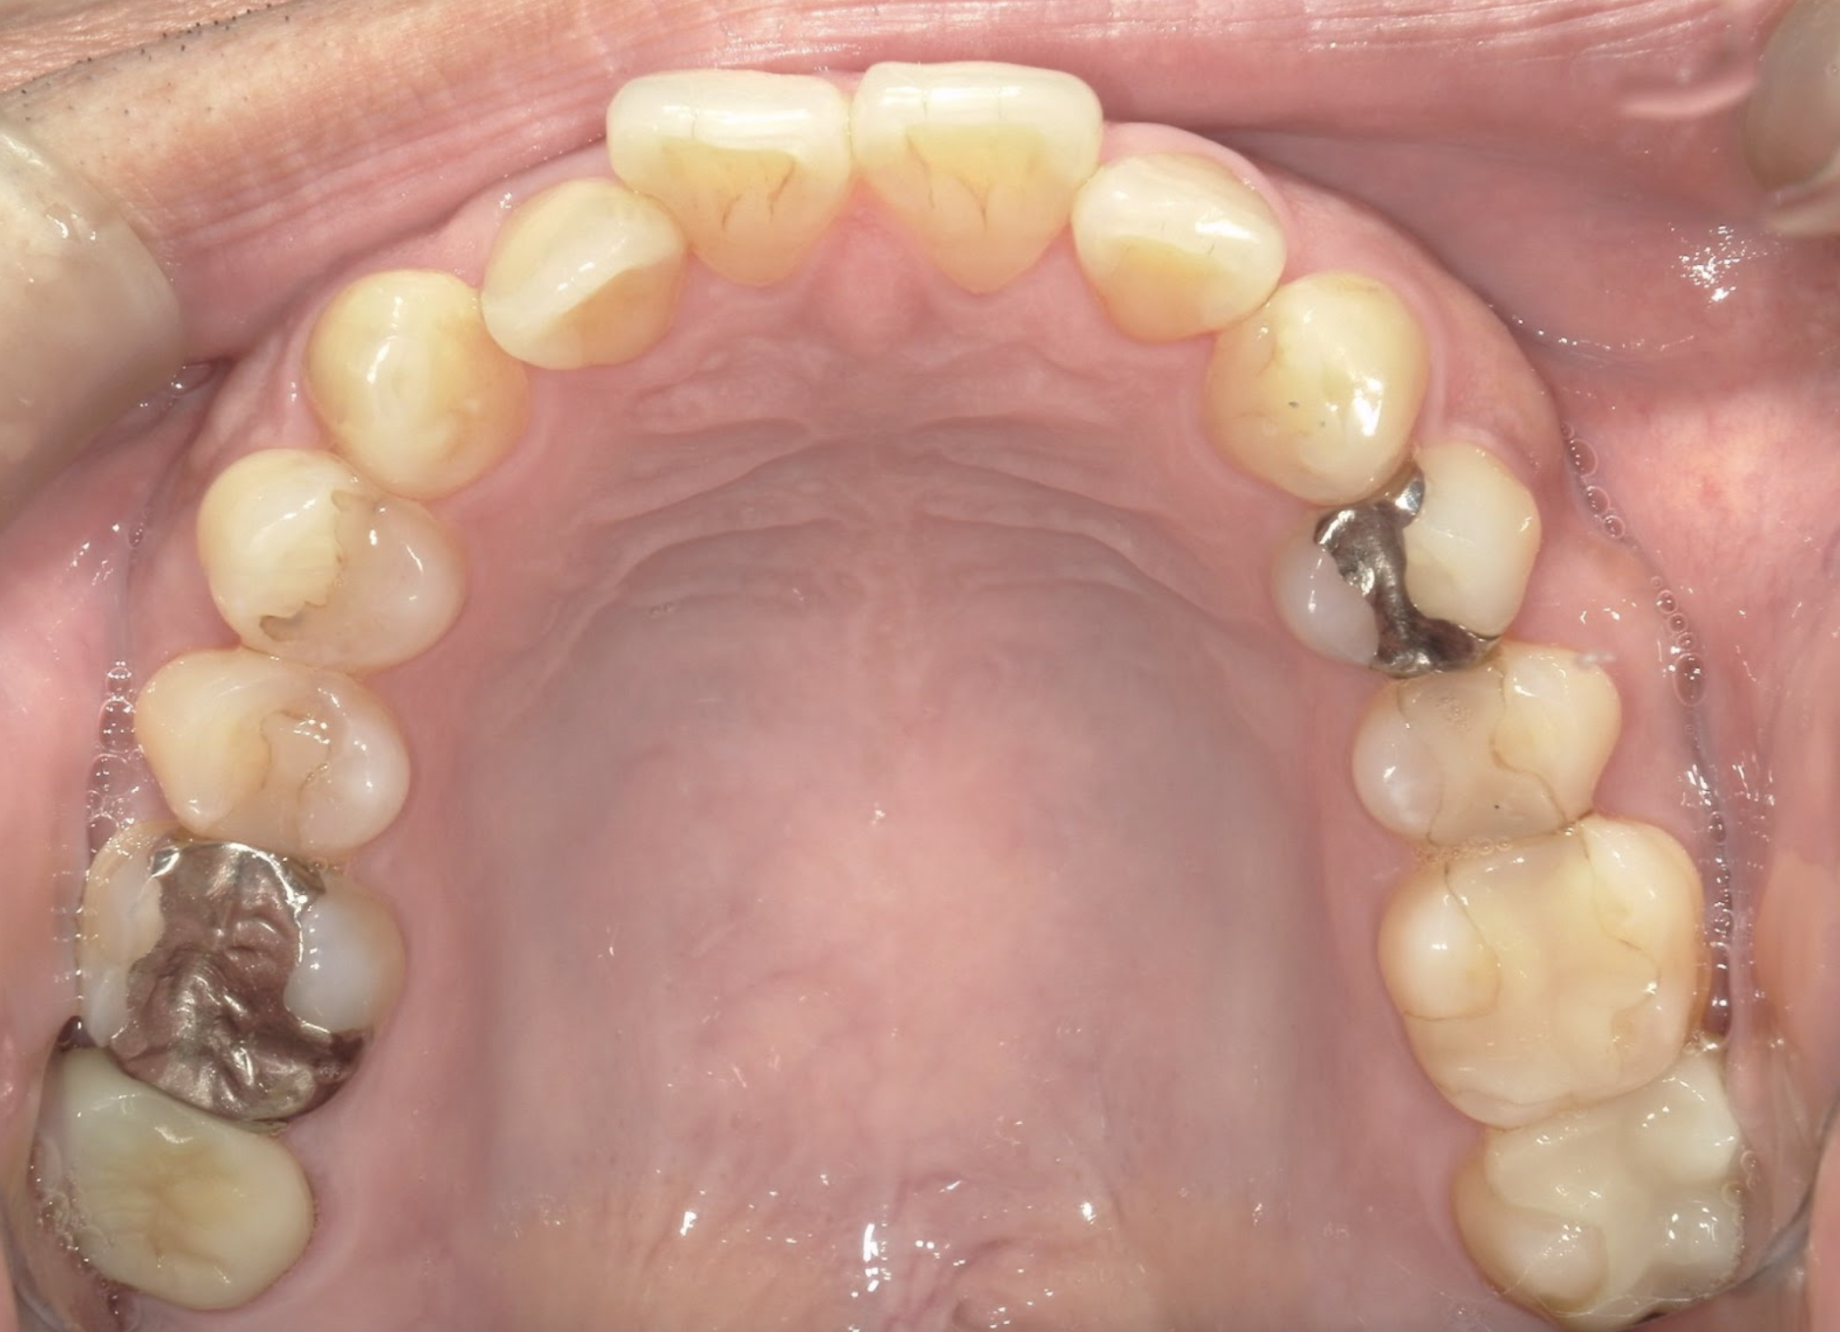

セレックの症例 2019.07.17セレックの症例 セレックとは欠損した歯に対して、セラミック素材による歯の修復を指し、CAD/CAMを用いて設計され、より歯に馴染むように作製されます。初診時…4本セレックセレックスキャン前…(1時間の形作り)セレックセット…... 続きを読む